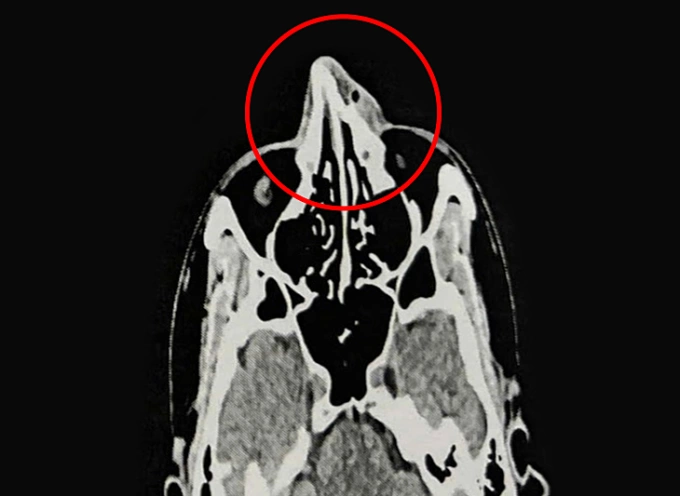

Chụp CT cho thấy mũi anh Phi bị gãy. Ảnh: Bệnh viện Đa khoa Tâm Anh

Kết quả nội soi và chụp CT 128 lát cắt ghi nhận xương mũi của anh Phi bị gãy ở vị trí tháp mũi, phù nề tụ khí mô mềm vùng mũi, lệch vách ngăn mũi, viêm mũi xuất tiết. ThS.BS.CKI Nguyễn Trung Nguyên, Trung tâm Tai Mũi Họng, Bệnh viện Đa khoa Tâm Anh TP HCM, cho biết vỡ xương mũi (gãy xương mũi) là loại gãy xương mặt phổ biến nhất do mũi ở vị trí trung tâm mặt và nhô ra trước. Chấn thương thường xảy ra do tai nạn, ngã hoặc va đập trong thể thao như anh Phi.